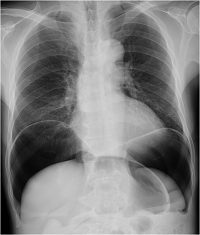

[¾Öµ¶ÀÚÀÇ ´äº¯ 5] õ°ø¿¡ ´ëÇÑ ´ëó°¡ ´Ü½Ã°£¿¡ ÀÌ·ç¾îÁ® ´õ ÀÌ»óÀÇ leak°¡ ¾ø¾î ½Ã¼ú ÁøÇà¿¡ ¹«¸®°¡ ¾ø´Ù¸é õÀÚ´Â ÇÊ¿ä¾ø½À´Ï´Ù. ºñ·Ï Áõ·ÊÀÇ »çÁø ó·³ air trapingÀÌ °üÂûµÇ¾îµµ ȯÀÚÀÇ vitalÀÌ stableÀÌ ÇÏ´Ù¸é (¾à°£ ºÒÆíÇϱâ´Â ÇϰÚÁö¸¸) ²À õÀÚ°¡ ÇÊ¿äÇÏÁö´Â ¾Ê´Ù°í »ý°¢µË´Ï´Ù. À쫆 ̵°øÀÌ »ý°Ü abdomenÀÌ tenseÇØ Áö°í ´õ ÀÌ»óÀÇ ½Ã¼ú ÁøÇà¿¡ ¹«¸®°¡ ÀÖ´Ù°í ÆÇ´ÜµÇ¸é (PR¡è, RR¡é, irritated state etc) ½Ã¼úÀå¿¡¼ ¹Ù·Î blind tappingÀ» ÇÕ´Ï´Ù. (ºÎÀ§´Â semi left. Lateral decubitusÀÚ¼¼¿¡¼ RUQºÎÀ§ÀÇ midline±Ùó¸¦ Áß½ÉÀ¸·Îsheath needle: 18G-19G)

ÀúÀÇ rationale´Â (1) õ°øÀÇ À§Ä¡/»óȲ¿¡ µû¶ó¼´Â ¹ß»ý Áï½Ã seal upÀ» ÇÏÁö ¸øÇϰí( ¶Ç´Â ¾ÈÇϰí) ¾î´À Á¤µµ dissectionÀ» ÁøÇà ÈÄ¿¡ ÇÏ´Â °ÍÀÌ ÇâÈÄ ½Ã¼úÀ» ¿ëÀÌÇÏ°Ô ÇÏ´Â °æ¿ì°¡ ÀÖ´Ù´Â Á¡ÀÔ´Ï´Ù. ÀÌ·± °æ¿ì severe air trapping¿¡ ÀÇÇÑ Dg herniationÀ¸·Î cardiopulmonary distress°¡ »ý±æ ¼ö ÀÖ½À´Ï´Ù. (2) ȯÀÚ´Â ¼ö¸é »óÅ À̹ǷΠº¹ºÎÀÇ ·ÎÄà ¸¶ÃëµîÀÌ ÇÊ¿ä¾ø½À´Ï´Ù. (3) <¾Öµ¶Àڴ亯1> ó·³ ÇÏ´Â °ÍÀÌ ÀÌ»óÀûÀ̳ª ȯÀÚ/ º¸È£ÀÚ compliance¸é¿¡¼ 2 or 3 stepÀ¸·Î ÇÏ´Â °Íº¸´Ù´Â one stepÀ¸·Î ³¡³»´Â °ÍÀÌ ÈξÀ ³ªÀº °ÍÀ¸·Î ÆÇ´ÜµË´Ï´Ù. ( What happens in Las Vegas, leave it there: ¶ó½ºº£°¡½º °ü±¤ È«º¸ ¹®±¸°¡ »ý°¢³ª³×¿ä^^) ¶ÇÇÑ À§¿¡ ¹àÈù °Íó·³ air trapingÀÌ °üÂûµÇ¾îµµ ȯÀÚÀÇ vitalÀÌ stableÀÌ ÇÏ´Ù¸é (¾à°£ ºÒÆíÇϱâ´Â ÇϰÚÁö¸¸) ²À õÀÚ°¡ ÇÊ¿äÇÏÁö´Â ¾Ê´Ù°í »ý°¢µË´Ï´Ù. (4) Áï ÆÇ´ÜÇÏ¿© õÀÚ°¡ ÇÊ¿äÇÏ¸é ½Ã¼úÀå¿¡¼ ÁøÇàÇÏÁö¸¸ º´½Ç·Î transferÈÄ secondary lookÀ¸·Î ÇÏÁø ¾Ê½À´Ï´Ù. ÀÌ»óÀº ÀúÀÇ ¸Å---¿ì °³ÀÎÀûÀÎ ÀǰßÀÔ´Ï´Ù.